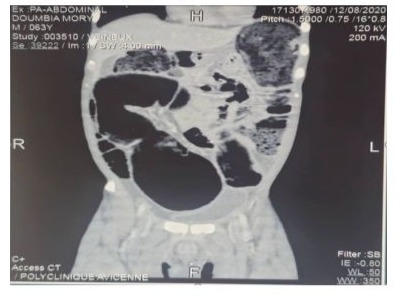

- MRI of the pelvis (Figure 3). showed: hypertrophic tumor of the prostatic gland with intrusion of the capsule, invasion of the seminal vesicles and floor crossing of the Denonvilliers' fascia and circumferential infiltration of the middle rectum associated with external and internal iliac pelvic lymphadenopathy.

Figure 3: Pelvic MRI sagittal and cross-sectional showing a prostate tumor with invasion of the rectum. White arrow: prostate, blue arrow: rectal lumen, red arrow: tumor invading the rectum.